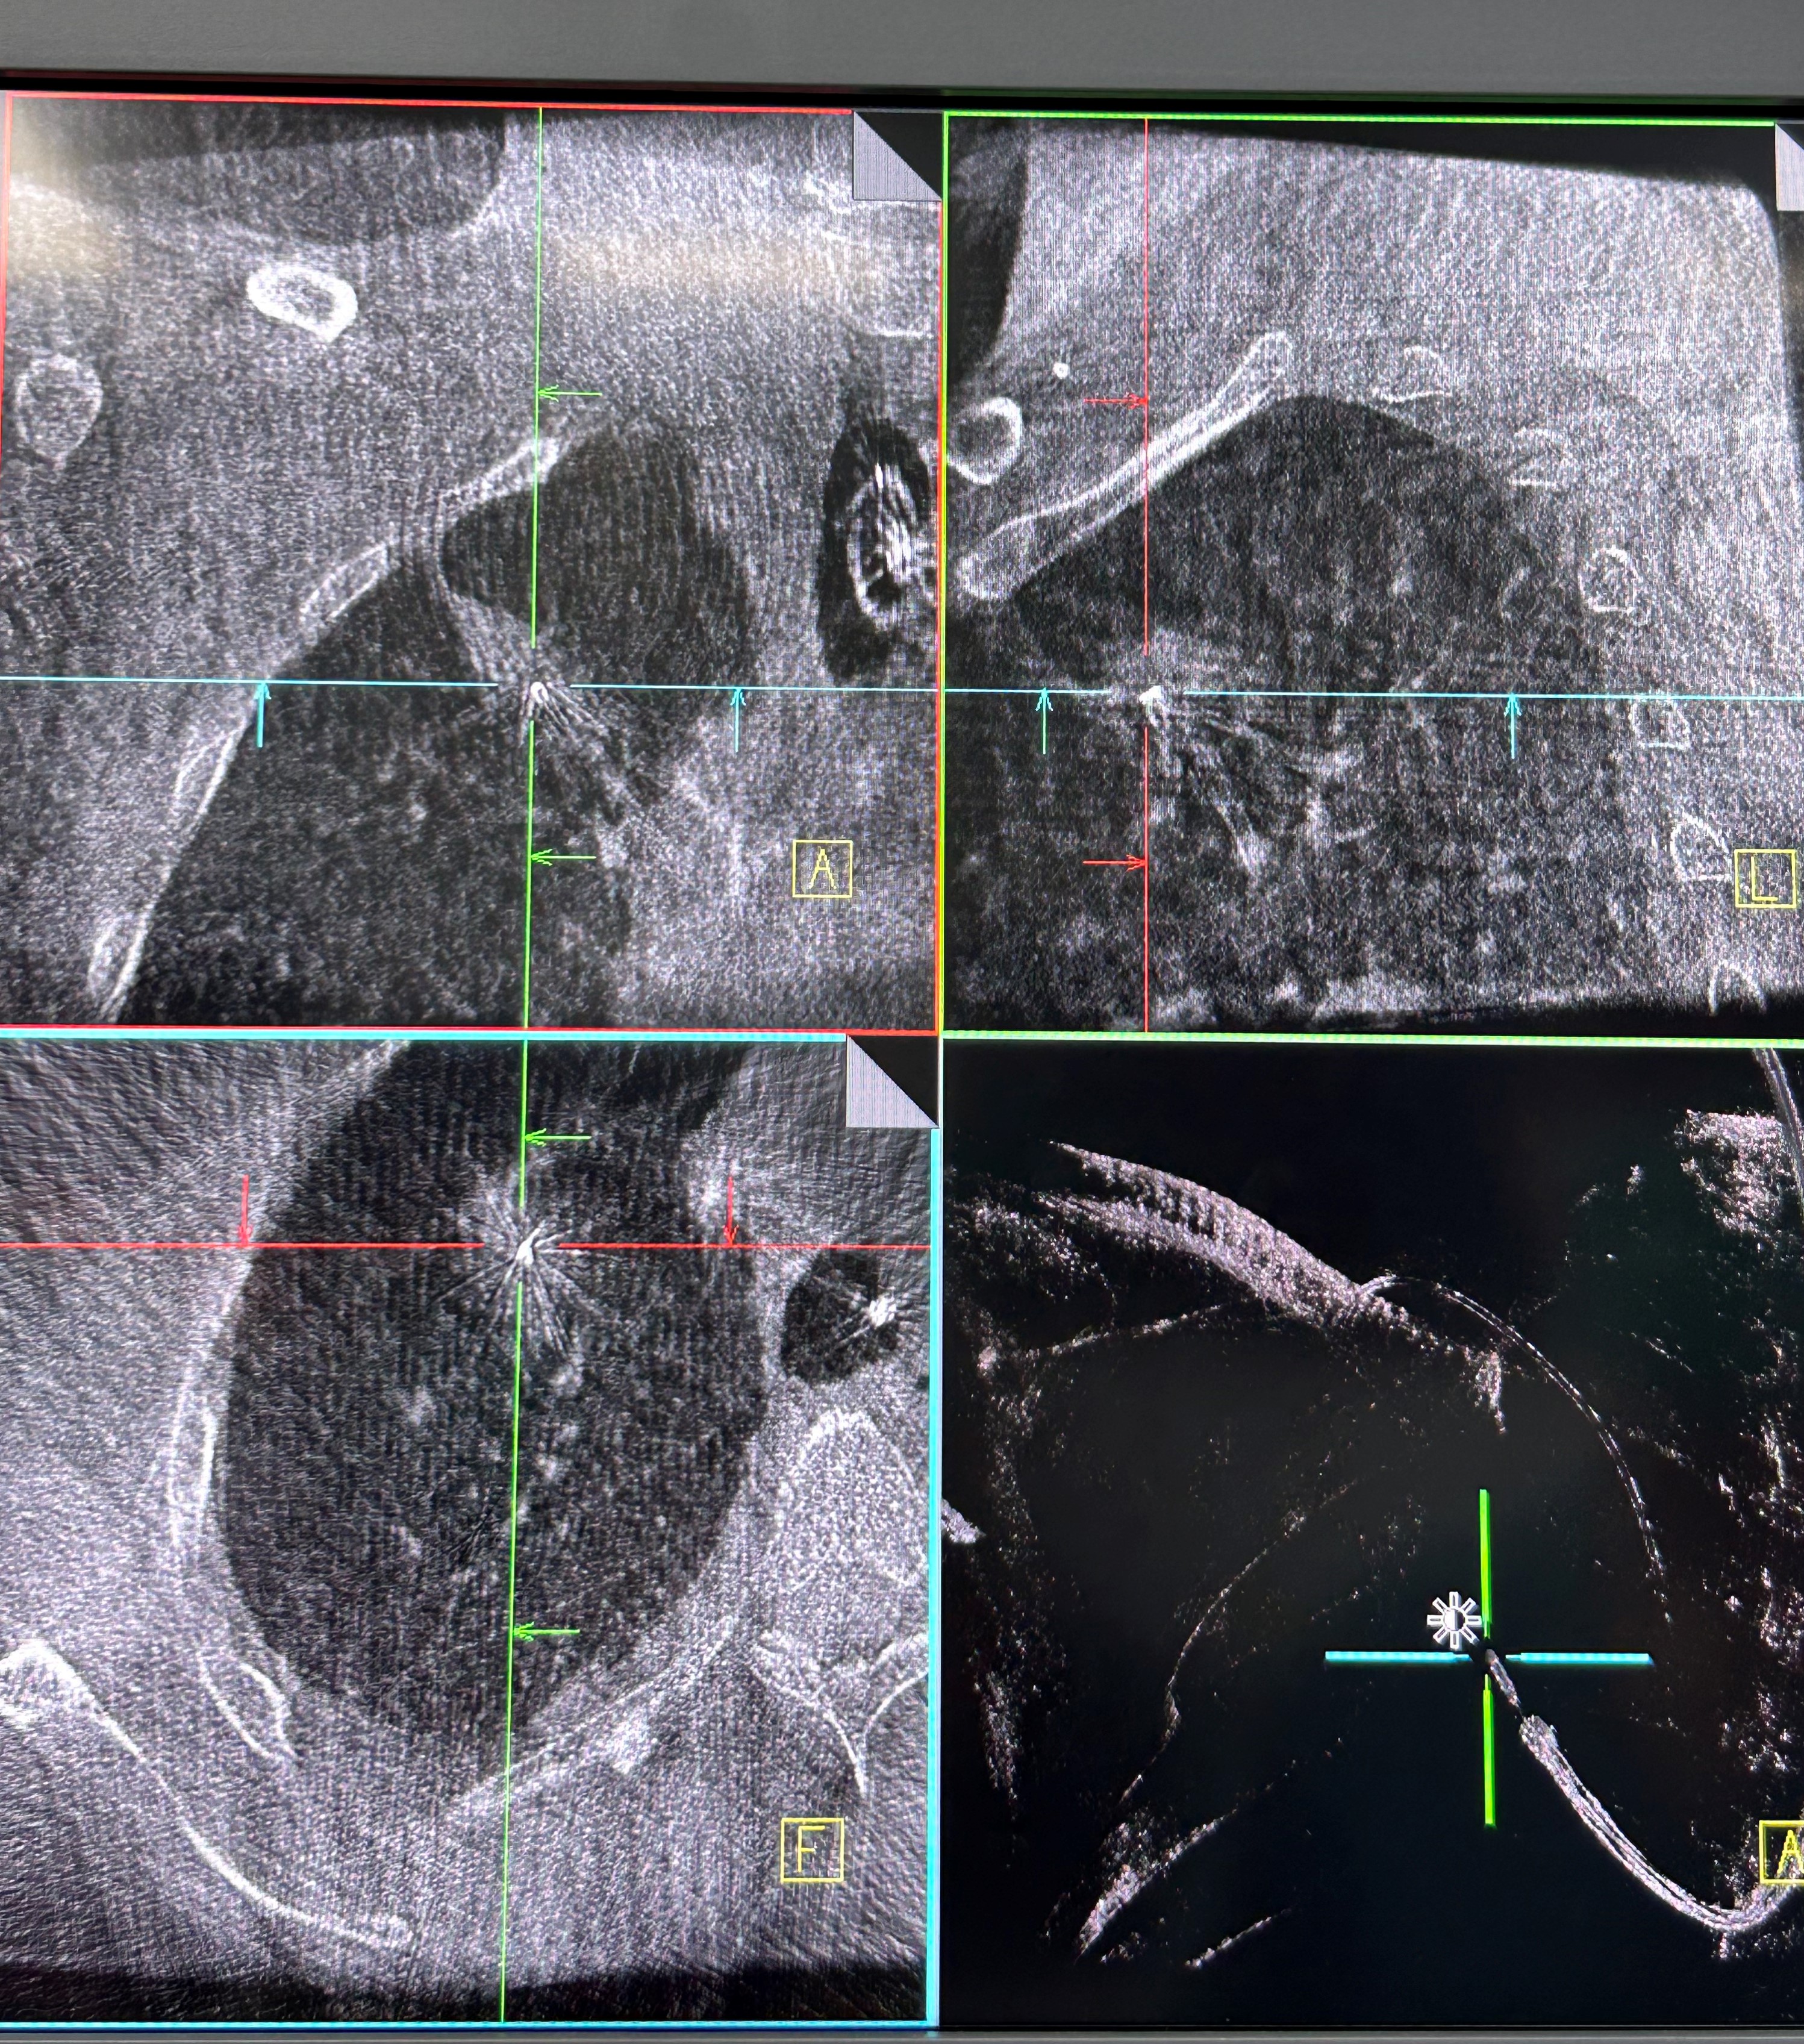

手术当日,呼吸科团队帮助患者在全麻下完成气管插管,手术由蒋军红主任指导,负责手术方案的实时优化与安全保障。曾大雄主任医师和王兰主任医师精准操作机器人支气管镜,在支气管镜导航机器人的精准引导下,通过AI三维重建、智能路径规划以及多模态信息融合,将支气管镜精准“引导”至右上叶尖段病灶处。随后,团队启动CBCT(锥形束计算机断层扫描)通过实时影像复核确认靶病灶,实现病灶“毫米级”精准锁定,彻底解决肺部病灶“找不到、找不准”的核心难题。机器人气管镜导航技术实现了从术前规划到术中操作全流程的智能精准控制,真正做到了肺部病灶的精准覆盖。

明确肿瘤诊断后,治疗方案即刻启动。团队经导航引导鞘管,精准插入一次性冷冻消融针(直径仅1.9mm)。再次通过CBCT确认消融针完全“扎根”于右上叶尖段病灶内后,开启冷冻治疗模式:以-160℃深低温冷冻10分钟、复温至45℃维持3分钟为一个治疗循环。完成了3次循环后,为确保病灶无遗漏,团队微调消融针位置,再次追加2次循环治疗。术后复查CBCT显示,病灶已呈现典型的冷冻后改变,术后两天复查胸部CT提示消融范围满意,治疗效果完全达到预期。整个手术过程中,患者生命体征始终平稳,术后第二天即可下床活动,真正实现了“微创治疗、快速恢复”的目标。

治疗前